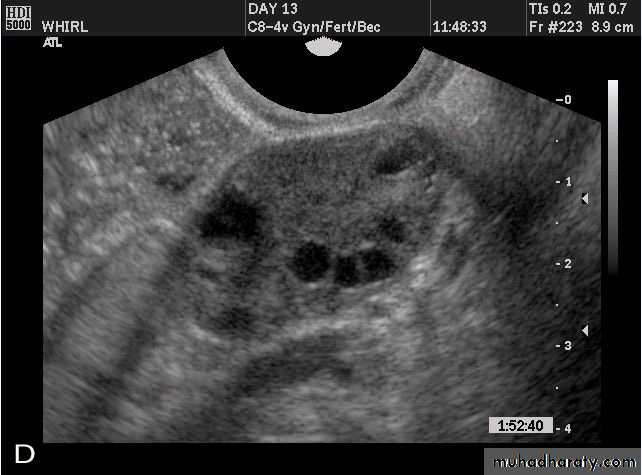

Images from women with differing expressions of the four major subtypes of the metabolic syndrome associated with polycystic ovary syndrome (A–D). The images exhibit quite differing ultrasonographic appearances in the size and distribution of follicles within PCOS ovaries. A recent corpus luteum is clearly visible in the ovary in panel (D).

Images from women with differing expressions of the four major subtypes of the metabolic syndrome associated with polycystic ovary syndrome (A–D). The images exhibit quite differing ultrasonographic appearances in the size and distribution of follicles within PCOS ovaries. A recent corpus luteum is clearly visible in the ovary in panel (D).• POLYCYSTIC OVARY SYNDROME